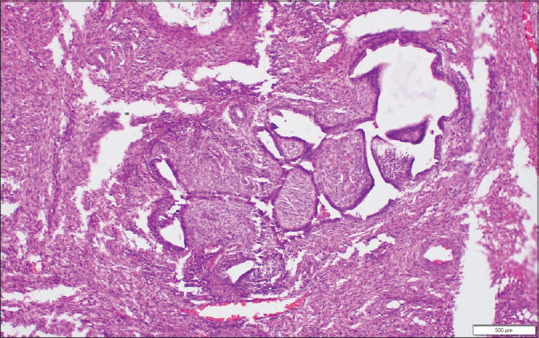

宫颈腺纤维瘤是一种极为罕见的良性苗勒氏混合性肿瘤,包括良性上皮组织和间质组织。世卫组织2020年对女性生殖道的分类甚至没有将腺纤维瘤作为一个单独的实体。一位50多岁的绝经后女性表现为每个阴道出血。检查发现多发性宫颈息肉。宫颈息肉的组织病理学提示宫颈腺纤维瘤,由于没有有丝分裂图形和细胞异型性。有时甚至分化良好的腺肉瘤也可能被误诊为腺纤维瘤。免疫组织化学标记有助于区分腺肉瘤和腺纤维瘤。没有典型的临床或影像学特征强烈提示诊断。虽然腺纤维瘤是一种良性肿瘤;然而,它仍被发现侵袭子宫肌层和盆腔静脉,复发和转移。对所有宫颈肿瘤进行详细的组织病理学检查是至关重要的,不仅可以排除恶性病变,而且可以排除腺纤维瘤,无论临床症状如何。

Adenofibroma of the cervix is an extremely rare benign Mullerian mixed tumor, which contains both benign epithelial and mesenchymal tissue. The WHO 2020 classification of the female genital tract does not even include adenofibroma as a separate entity. A postmenopausal lady in her mid-50s presented with bleeding per vagina. On examination, there were multiple cervical polyps. Histopathology of cervical polyps suggested adenofibroma of the cervix due to the absence of mitotic figures and cellular atypia. Sometimes even well-differentiated adenosarcomas can be misdiagnosed as adenofibroma. Immunohistochemistry markers help in differentiating adenosarcoma from adenofibroma. There are no typical clinical or imaging characteristics that strongly suggest the diagnosis. Although adenofibroma is a benign tumor; still it has been found to invade the myometrium and pelvic veins, relapse, and metastasize. It is crucial to perform a detailed histopathological examination of all the cervical tumors not only to exclude malignant lesions but also to exclude adenofibroma regardless of clinical symptoms.